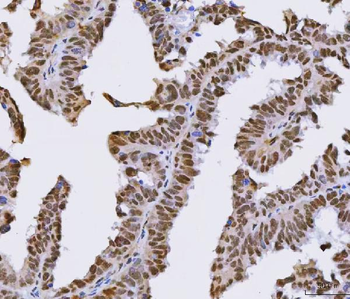

Antibody used in IHC on Human Intestine at 4.0-8.0 ug/ml.

Antibody used in IHC on Human Skin at 4.0-8.0 ug/ml.